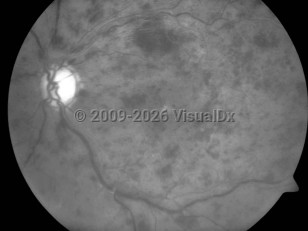

Central retinal vein occlusion - External and Internal Eye

The occluded central vein can lead to intraretinal hemorrhage, exudation of fluid, varying levels of ischemia, and neovascular complications such as neovascular glaucoma. CRVO is commonly classified by severity into 2 forms: the nonischemic form of CRVO, which is milder and more common, and the ischemic form, which results in more severe retinal damage and vision loss. In ischemic CRVO, more than 90% of patients have vision of 20/400 or worse. One-third of patients with the nonischemic type progress to the ischemic type.

Iris neovascularization, which is associated with neovascular glaucoma, occurs in up to 60% of patients with the ischemic form, usually 3-5 months following the obstruction. The main risk factors for development of neovascular glaucoma after a CRVO are the extent of capillary nonperfusion, poor visual acuity, severe venous tortuosity, and retinal hemorrhage.